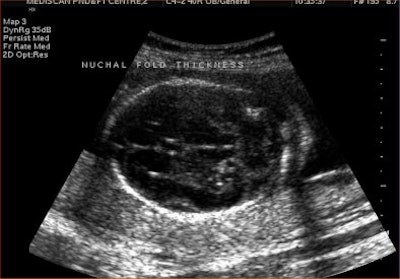

Nuchal fold thickness is the first sonographic marker to have been associated with increased risk of Down syndrome. An increased nuchal fold thickness of 6 mm or higher warrants a fetal karyotype, regardless of associated abnormalities, Suresh said. The nuchal fold thickness should be measured only between 15-20 weeks because the normal skin thickness remains unchanged in this period.

For measuring nuchal fold thickness, a transaxial view of the head is taken through the thalamus, cerebellum, and occipital bone. The nuchal fold thickness is measured in the cerebellar plane from the outer surface of the occipital bone to the outer surface of the skin.

![]() |

| Increased nuchal fold thickness. |

The following table shows how risk for Down syndrome changes depending on whether the ultrasound shows normal or increased nuchal fold thickness in the fetus.